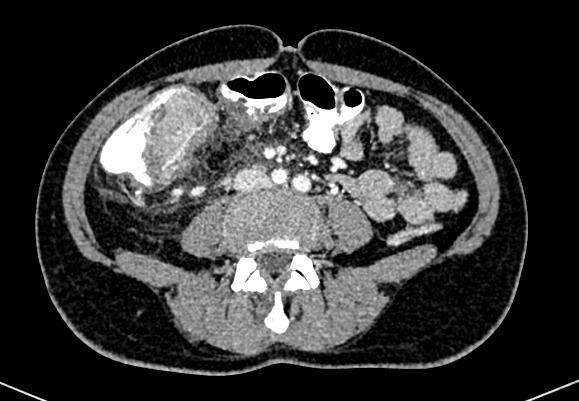

Vous avez fait réaliser l’examen suivant, confirmant le syndrome occlusif (figures 1 et 2) : Fig. 1 (source : M. Roulleaux Dugage)Fig. 2 (source : M. Roulleaux Dugage)

Question 4 - Concernant cet examen d’imagerie, vous pouvez dire :

Il s’agit bien d’un scanner abdomino-pelvien injecté, au temps portal, mettant en évidence une volumineuse masse du côlon droit associée à au moins une masse hépatique d’allure secondaire. Pour rappel : – au temps artériel : opacification de l’aorte, de la périphérie du rein ; – au temps portal : prise de contraste massive du parenchyme hépatique et rénal ; – au temps veineux : prise de contraste veine cave inférieure…